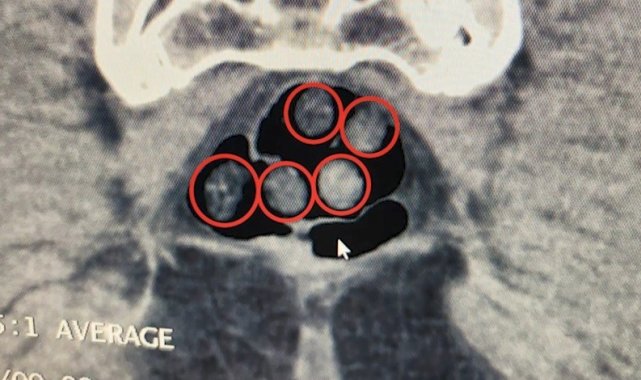

Bitlis Valiliğinden yapılan açıklamada, Bitlis Emniyet Müdürlüğü Narkotik Suçlarla Mücadele Şube Müdürlüğü ve İstihbarat Şube Müdürlüğü ekiplerinin uyuşturucu ile mücadele kapsamında yürüttüğü iki ayrı titiz çalışmanın başarıyla sonuçlandırıldığını bildirdi. Açıklamada, "Tatvan'da durdurulan çekici üzerindeki araçta yapılan aramada; 734 gram metamfetamin maddesi ele geçirildi. Olay ile ilgili 2 şahıs gözaltına alındı. Yine Tatvan'da durdurulan bir otobüste yolcu olarak seyahat eden yabancı uyruklu 2 şahıs gözaltına alındı. Tatvan Devlet Hastanesinde yapılan röntgen ve tomografi incelemelerinde, şahısların mide ile bağırsaklarında çok sayıda yabancı cisim tespit edildi. Yapılan tıbbi müdahale ile şahısların yuttuğu 14 kapsül ve üzerlerinden 36 kapsül olmak üzere toplam 50 kapsül 385 gram metamfetamin maddesi ele geçirildi. Her iki olayda da uyuşturucu madde imal ve ticareti suçundan gözaltına alınan 4 şahıstan 3'ü çıkarıldığı adli mercilerce tutuklandı. Hemşehrilerimizin huzuru ve güvenliği için uyuşturucu madde imalatı, kaçakçılığı ve kullanımına karşı yürütülen kararlı mücadelemiz devam edecektir" denildi.

BİTLİS (İHA) – Bitlis'te yakalanan yabancı uyruklu 2 şahsın mide ve bağırsaklarıyla üzerlerinde toplam 50 kapsül 385 gram metamfetamin maddesi ele geçirildi.